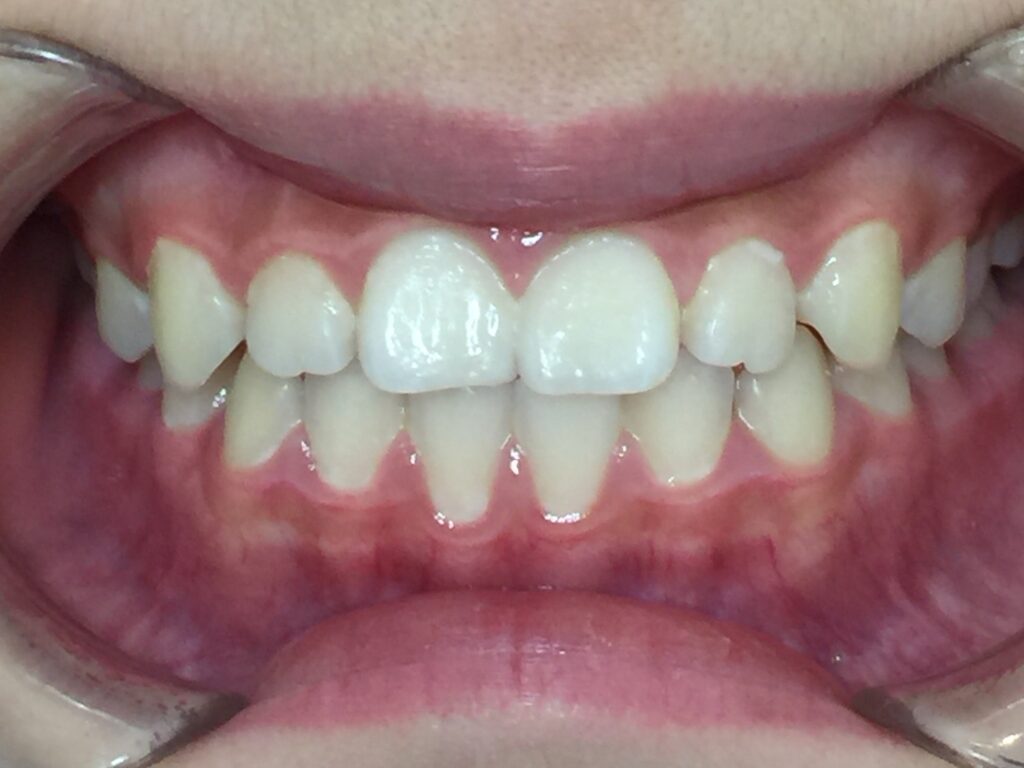

10代女性「前歯同士が噛み合っていて将来が不安」舌と顎の正常な発育をサポートするマウスピースと歯列の横幅を広げる矯正を行い、正常な歯並びに改善した症例

拝見すると、上下の前歯同士が噛み合っている「切端咬合(せったんこうごう)」と、前歯から奥歯までの歯並びが狭くなっている「歯列弓の狭窄(しれつきゅうのきょうさく)」の状態でした。そのため、将来ガタガタの歯並び「叢生(そうせい)」になることが予想できました。

とてもきれいな歯並びになり、お母様もご本人様も大変満足されていました。